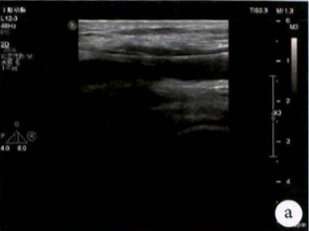

图:a) 穿刺后导丝置入;

图:b) 吸栓装置定位;

图:c) 球囊扩张股浅动脉时球囊远心端显像;

图:d)球囊扩张股浅动脉开口处显像,同时附带血流显像;

图:e)术前评估时腘动脉未见血流图像;

图:f)经吸栓、球囊扩张等治疗措施后腘动脉血流图像